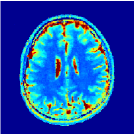

V-B Visualising MRFResnet segments on Bloch manifold

By vector quantisation (e.g. k-means clustering) we cluster regions of that output distinct slopes and identify the segments . Similar routine could apply to compute input space partitions by clustering back-propagated output derivates after each residual block (Theorem 1 and Remark 1 also hold for the intermediate blocks of ).

According to [44] as we progress into deeper layers, partitions will be subdivided into smaller segments in a hierarchal fashion. This can be observed in Figure 2 where we adopted the above routine for the T1/T2 encoding MRF sequence used in our experiments and visualised multi-scale (from coarse-to-fine) partitions obtained after each residual layer. The Bloch response manifold is sampled across fine-gridded T1/T2 values (i.e. MRF dictionary) to visualise the intersection of the input space segments with this manifold (results are visualised across the three dominant principal component axes). MRFResnet encoder learns about a thousand partitions for its end-to-end mapping . In the light of (16) we know that for each partition the network implicitly encodes deep matched-filters (the rows of or alternatively ) and an offset term to locally linearly regress the T1/T2 outputs in that segment. As such instead of memorising 100K dictionary atoms used for training, the network learns a compact piece-wise affine approximation to the Bloch manifold projection (5) as a rapid and memory-efficient alternative to DM’s point-wise approximation (7). The total number of parameters used by the MRFResnet (Table I) are two hundreds times less than the size of the dimension-reduced MRF dictionary. Figure 3 shows the Bloch responses for a range of T1/T2 values, as well as deep matched-filters learned by MRFResnet to predict each of these quantities in this range from noisy inputs. Computed through (17), match-filters are one-dimensional analogues of the saliency maps a.k.a. deep dream images [49], measuring sensitivities of the T1/T2 output neurons with respect to the inputs.